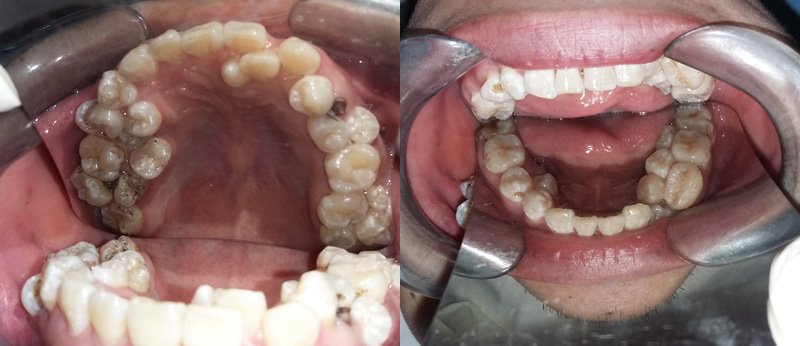

Hình ảnh chụp phim cho thấy bệnh nhân mọc thừa răng chi chít

Tại đây các bác sĩ đã hết sức bất ngờ khi phát hiện ngoài chiếc răng sâu, bệnh nhân bị mọc thừa đến 13 chiếc răng ở vị trí răng 4 và 5 trên 2 hàm. Các răng mọc lệch, chen chúc, dàn hàng ngang khiến việc vệ sinh khó khăn, gây sâu, viêm tủy.

Theo BS Thái, trường hợp thừa nhiều rằng nhất đã từng gặp là 8 chiếc, riêng trường hợp anh Sơn thừa đến 17 chiếc răng thì chưa gặp bao giờ. Qua trường hợp trên, BS Thái khuyến cáo, người dân nên có thói quen khám răng định kỳ 6 tháng 1 lần. Khi thấy răng mọc 2-3 cái một chỗ cần đi khám ngay để can thiệp kịp thời.